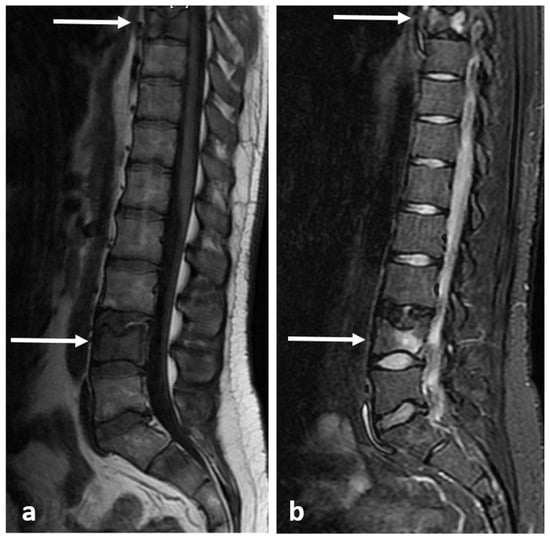

3.9. Aneurysmal Bone Cyst

| Aneurysmal bone cyst | Expansile lytic lesion with internal bone septations. | Fluid—fluid levels within the cysts, high T1 signal within layering fluid content due to haemorrhage. |